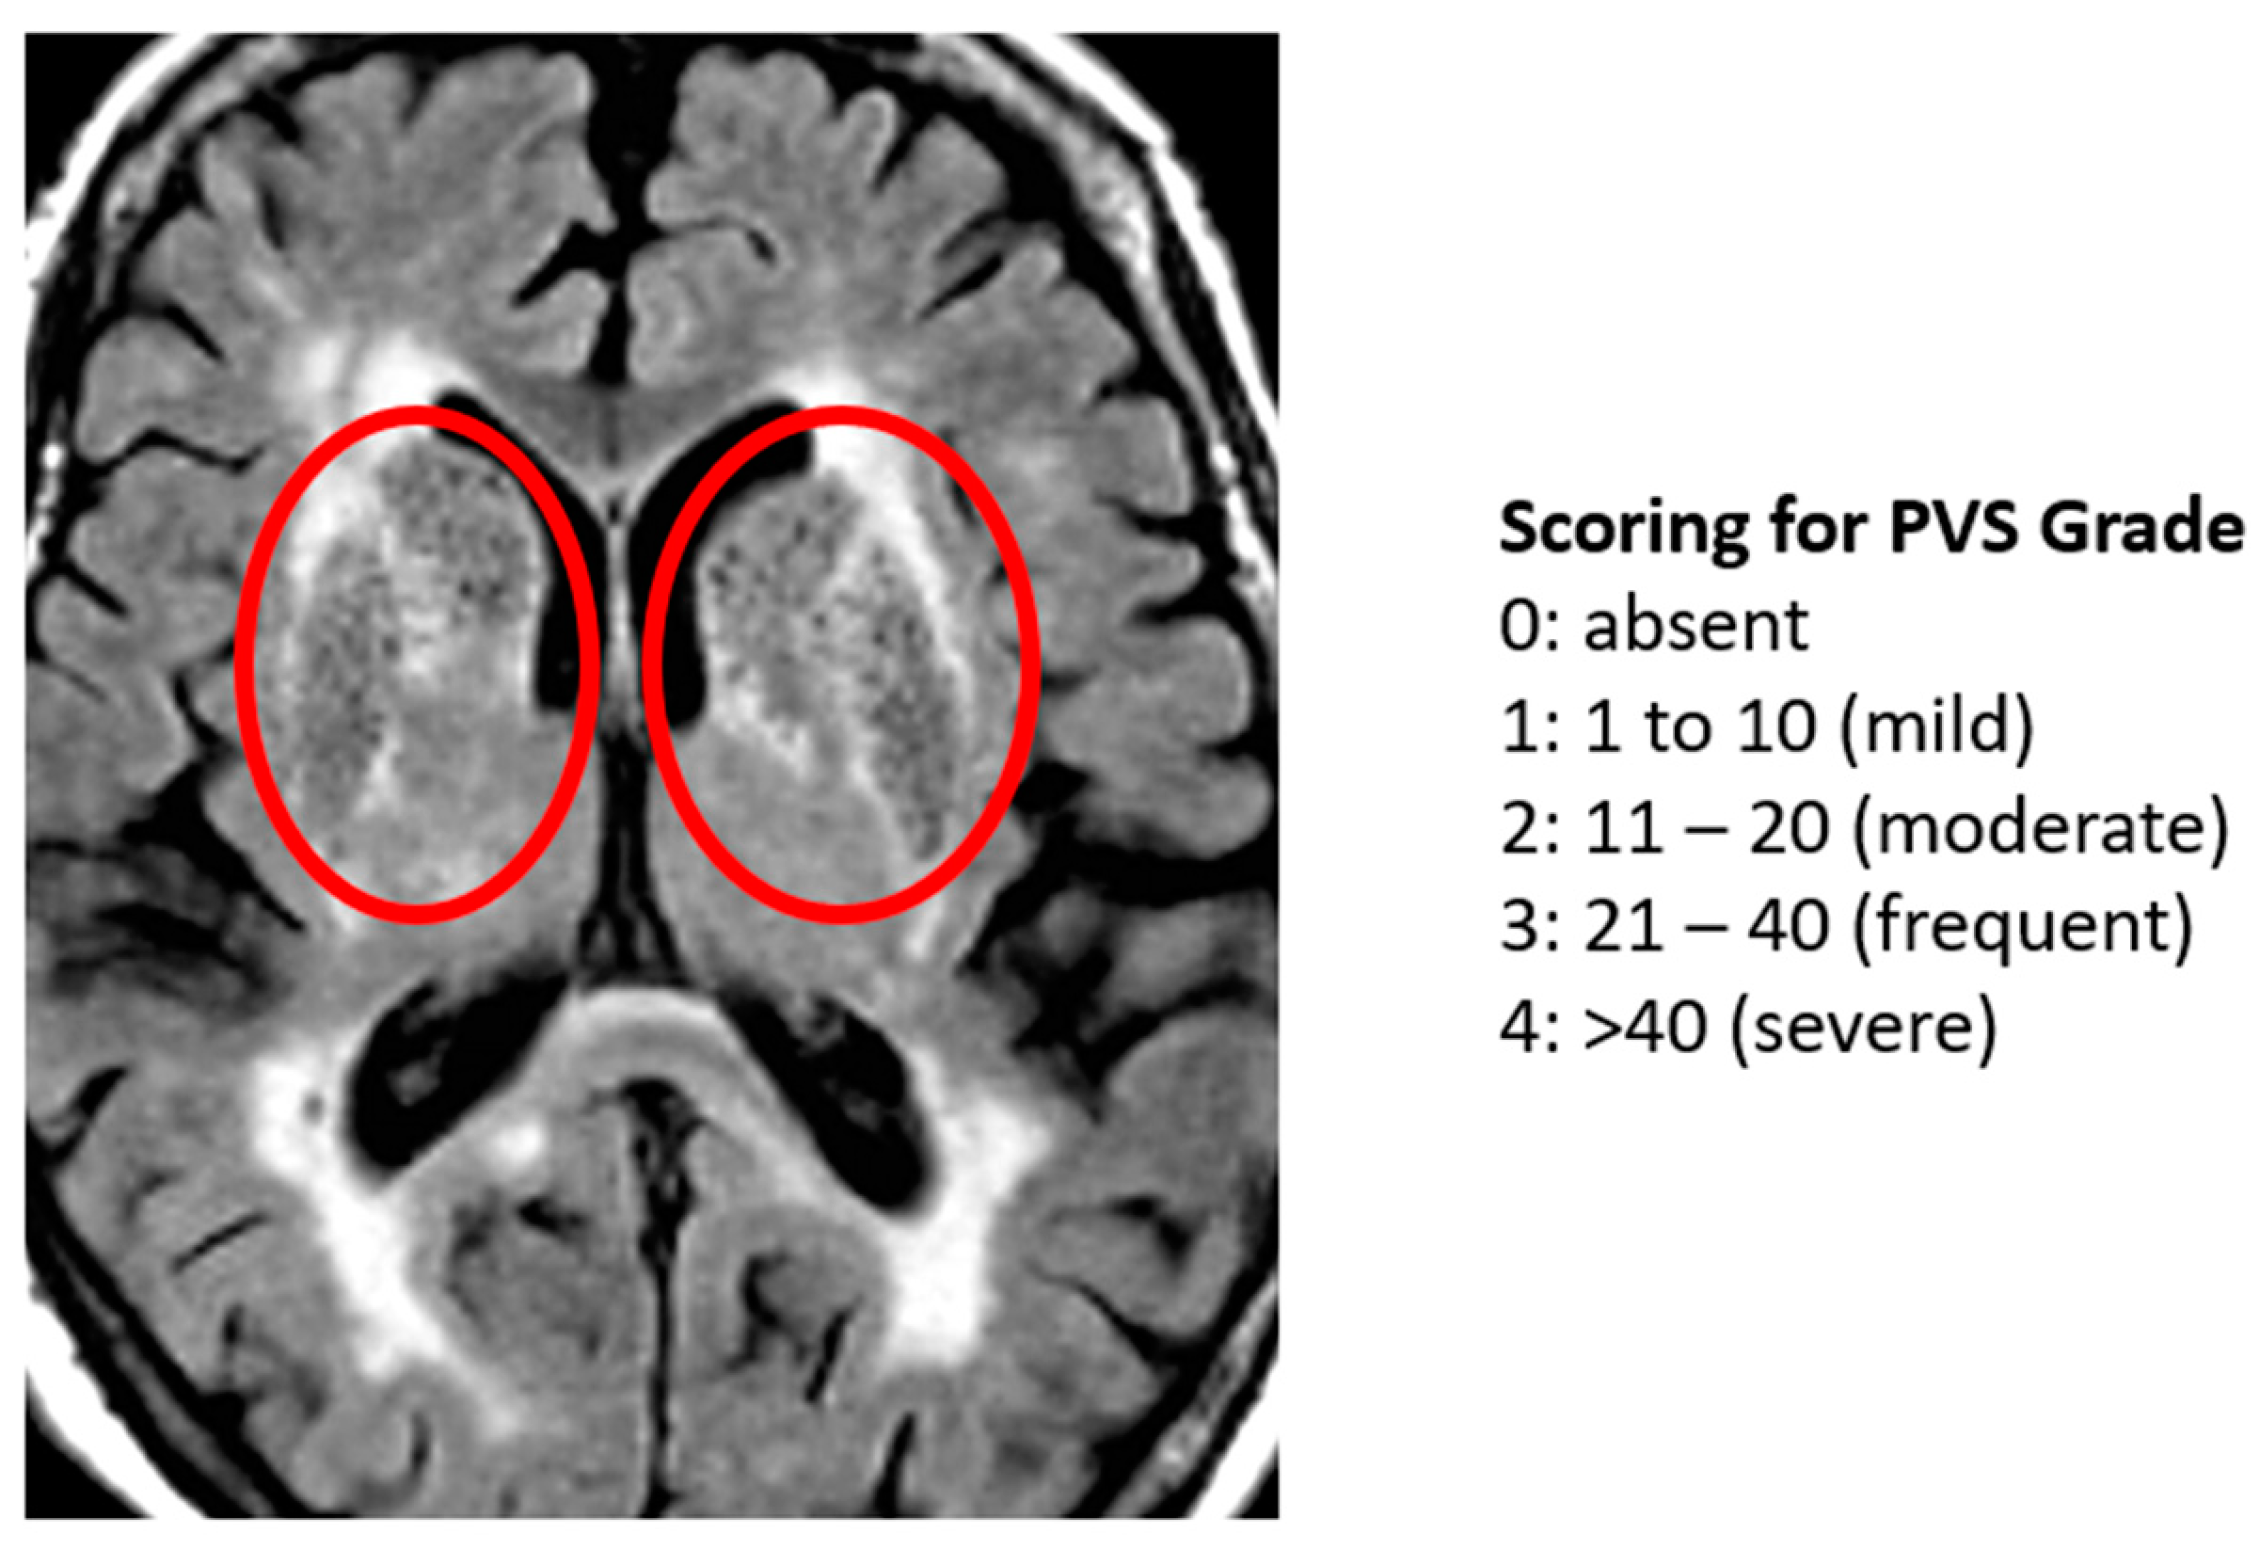

- Potter, G.M.; Chappell, F.M.; Morris, Z.; Wardlaw, J.M. Cerebral perivascular spaces visible on magnetic resonance imaging: Development of a qualitative rating scale and its observer reliability. Cerebrovasc. Dis. 2015, 39, 224–231. [Google Scholar] [CrossRef]

| PVS Grade (Potter Scale) | 2.69 ± 1.01 | |